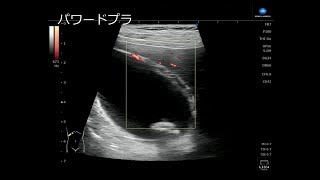

病院で胆石があるといわれ、そのまま入院となった。大きな石が2個エコー検査で写っている。胆嚢を摘出するのが完治になるそうだが、この時は胆のう炎を起こしているため、脇腹から炎症を起こしている胆汁を抜くことになった。この時は、石を残したまま、退院した。が、しかし、一か月も経たないうちに、再入院することになった。一週間ほど、熱があがったり、さがつたり、悪寒や嘔吐があったりしていたので、かかりつけの先生もこれは風邪ではなく、胆のう炎からきているということで前回の病院へ入院した。今回は、腹腔鏡下胆嚢摘出術で胆嚢ごと石も摘出した。